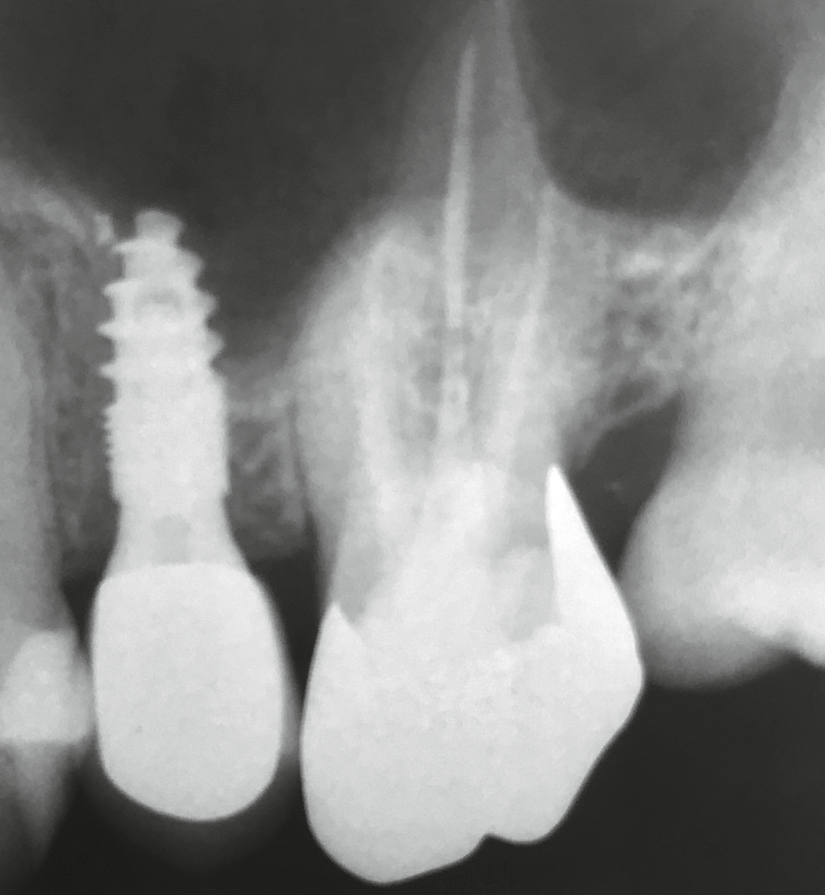

Die Wundheilung verlief erwartungsgemäß schmerzlos, mit nur geringer Kieferkammresorption. Es sollte auf meinen Wunsch hin ein minimalinvasiv zu inserierendes Implantat eingebracht werden, ohne Aufklappung des Kieferkamms, denn meiner Ansicht nach ist dies der erste Schritt in Richtung Periimplantitis. Ich wandte mich daraufhin an Dr. Armin Nedjat, Flonheim, welcher mir ein solches Implantat inserierte. Mit diesen Erfahrungswerten und einem eingebrachten Spätimplantat regio 25 im MIMI-Flapless-Verfahren kehrte ich in meine heimische Praxis zurück. Die von meinem Zahntechnikermeister erstellte Krone für das Implantat 25 passte exakt und nach 8 Wochen Einheilzeit war die Behandlung abgeschlossen.

Widerwillig reifte in mir der unschöne Gedanke an einen Längsriss der palatinalen Wurzel des Zahnes 26. Die Beschwerden und der unauffällige Röntgenbefund ließen nur diese Diagnose schlüssig erscheinen. Ich wandte mich bezüglich einer erneuten Behandlung an Dr. Armin Nedjat. Nach Infiltrationsanästhesie, mittels MagicPen, entfernte Dr. Nedjat die Goldkrone. Er extrahierte den dreiwurzeligen Zahn und versuchte, in den vorhandenen Alveolarknochen, welcher durch die Trifurkation eingeschlossen war, zu implantieren. Der erfahrene Behandler benutzte zunächst den gelben konischen Dreikantbohrer. Danach erfolgte im D3- Knochen die Verdichtung des Knochens mit dem Ziel, eine Primärstabilität von 30–40 Ncm mit den Kondensern vom Durchmesser 2,4 mm, 3,0 mm, 3,8 mm, 4,3 mm zu erreichen. Nach dem Kondenser mit Durchmesser 5,3 mm war erst eine ausreichende Stabilität von 35 Ncm erzielt worden (Abb. 2). Minimalinvasiv wurde ein direkter Sinuslift durchgeführt – genial einfach durch Linkslauf des orangen Krestalbohrers vom Durchmesser 3,7 mm. Auf diese Weise kann die Schneider- Membran um bis zu 10 (!) mm angehoben werden. Ein Champions® (R)Evolution Titan-Implantat, Durchmesser 5,5 mm, Länge 10 mm, wurde inseriert (Abb. 3).